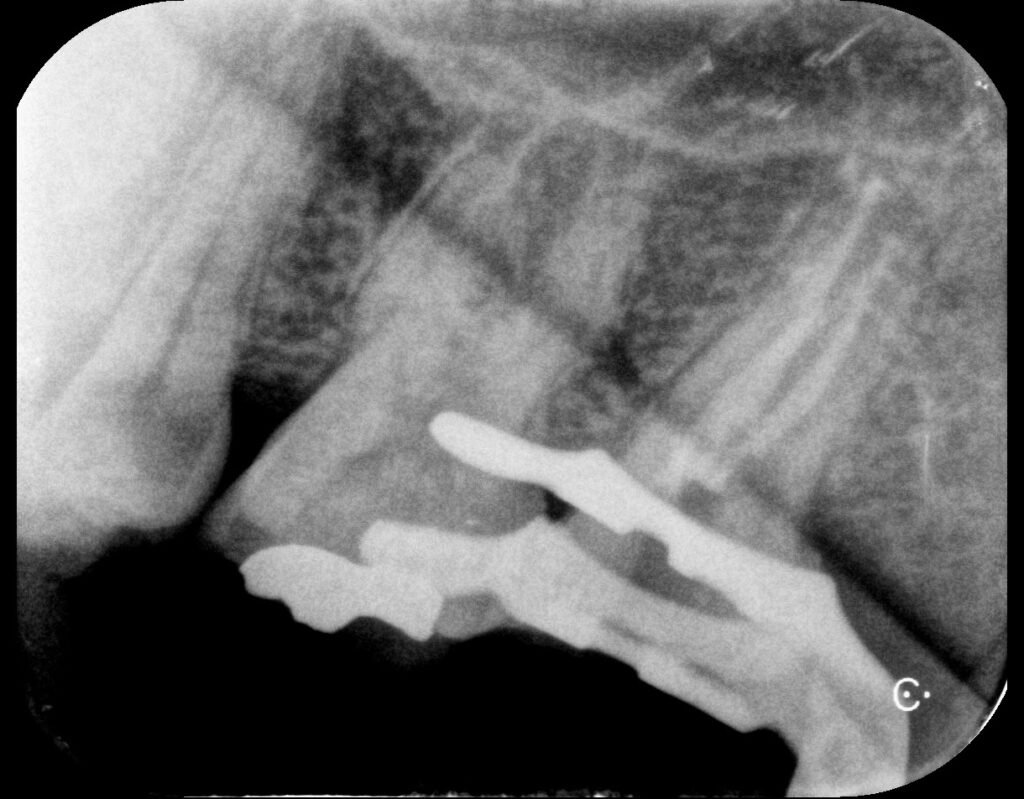

크랙이 치수(신경)까지 침범한 것으로 판단되어 신경치료(근관치료)를 진행했습니다. 방사선 사진에서도 치근 주변 변화가 확인되었어요. 치아 균열이 깊어질수록 세균이 신경까지 침투하기 쉬워지기 때문에 조기 치료가 중요합니다.

신경치료가 꼼꼼하게 잘 되었네요^^